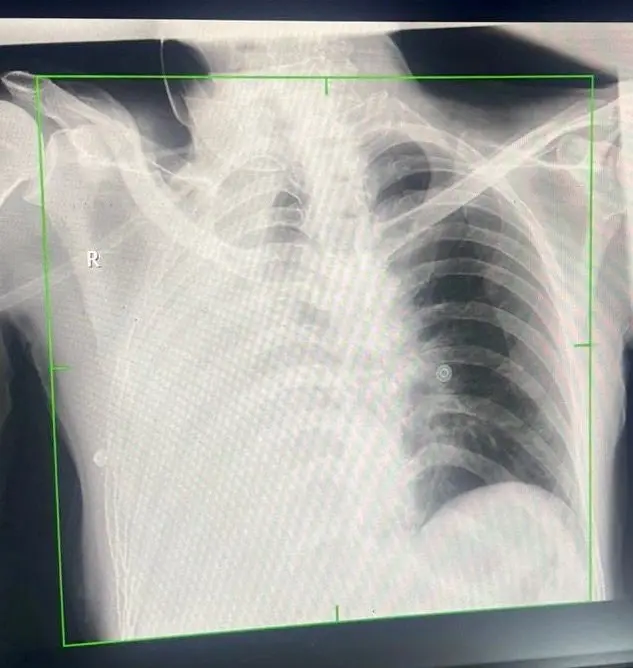

भोपाल। पत्थरों की चमक के पीछे हजारों मजदूरों की जिंदगी को निगलने वाली एक खामोश बीमारी सिलिकोसिस भी छुपी होती है। यह एक ऐसी बीमारी है, जिसका कोई स्थायी इलाज नहीं है। इसमें फेफड़े पत्थर जैसे सख्त हो जाते है और मरीजों को सांस लेना तक मुश्किल हो जाता है। ऐसा ही एक मरीज गंभीर हालत में AIIMS भोपाल पहुंचा। उसे सांस लेने में परेशानी हो रही थी। जांच के दौरान पता चला कि मरीज के दोनों फेफड़ों में एक खास तरह का प्रोटीन जमा था, जिससे फेफड़े भी सख्त हो गए थे। मरीज की स्थिति ऐसी थी कि अगल जल्द उपचार नहीं किया जाता तो उसकी मौत भी हो सकती थी। ऐसे में AIIMS में होल लंग्स लैवेज प्रक्रिया को अपनाकर सलाइन वाटर से फेफड़ों को धोकर प्रोटीन को साफ किया। AIIMS प्रबंधन की मानें तो मध्य भारत में पहला मौका है जब लंग्स पर जमे प्रोटीन को पानी से धोकर साफ किया हो।

इस पूरी प्रकिया को एम्स के पल्मोनोलॉजी विभाग के प्रो डॉ. अल्केश खुराना और असिस्टेंट प्रोफेसर डॉ. अभिनव खुराना द्वारा संपन्न किया गया। डॉ. खुराना के मुताबिक मरीज स्टोन क्रशर में काम करता था, जिससे वहां उड़ने वाली धूल उसके फेफड़ों में जम गई थी। इसे डिफ्यूज एल्जियोविर प्रोटिनोसिस भी कहते हैं। उन्होंने बताया कि इसके लिए एंजियोग्राफी के दौरान सलाइन वाटर से फेफड़े को साफ किया गया। यह प्रक्रिया बहुत जटिल होती है, क्योंकि फेफड़े में 6 से 8 लीटर पानी डालने से मरीज की मौत भी हो सकती है। इसलिए करीब 6 घंटे में पूरी प्रकिया हो सकी।

इस प्रोसीजर में कार्डियक थोरेसिक सर्जन डॉ. योगेश निवारिया भी शामिल थे। उन्होंने बताया कि यह प्रक्रिया इसलिए कठिन है क्योंकि एक फेफड़े को साफ करने के दौरान मरीज दूसरे फेफड़े पर ही निर्भर रहता है। इस मरीज का दूसरा फेफड़ा भी पूरी तरह से कमजोर था। ऐसे में मरीज को हार्ट लंग्स मशीन (आर्टिफिशियल लंग्स) पर रखना पड़ सकता है। हालांकि इस मरीज को इसकी जरूरत नहीं पड़ी।